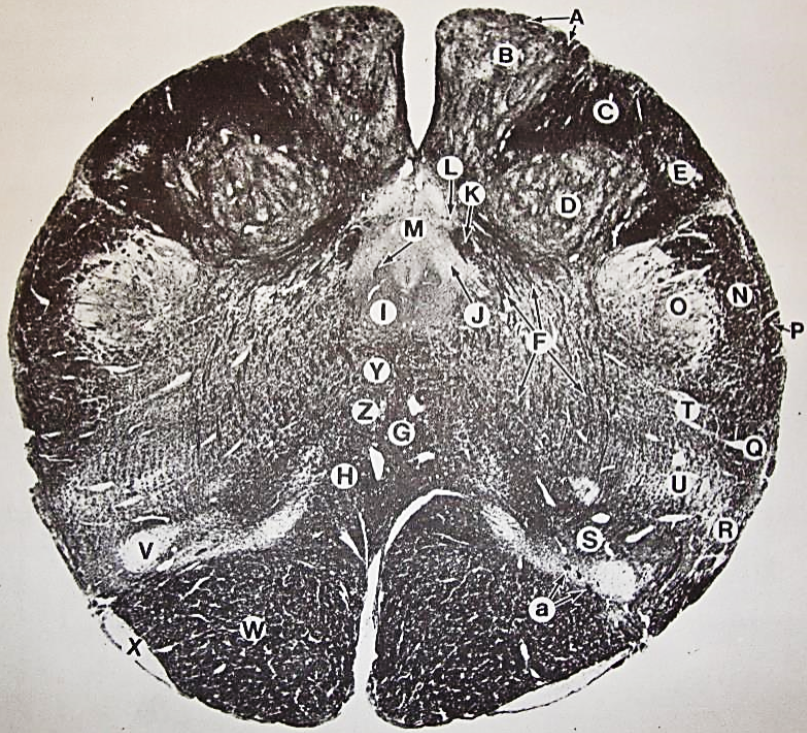

A

posterior median sulcus

B

posterior intermediate sulcus

C

anterior median fissure

D

gracile fasciculus

E

Gracile nucleus

F

fasciculus cuneatus

G

spinal trigeminal tract

H+I collectively

spinal trigeminal nucleus

J

Accessory nucleus

K

pyramidal decussation

L

lateral corticospinal tract

M

rubrospinal tract

N

posterior spinocerebellar tract

O

anterior spinocerebellar tract

P

lateral spinothalamic tract

Q

anterior spinothalamic tract

R

lateral vestibulospinal tract

S

medial longitudinal fasciculus

T

tectospinal tract

U

central canal